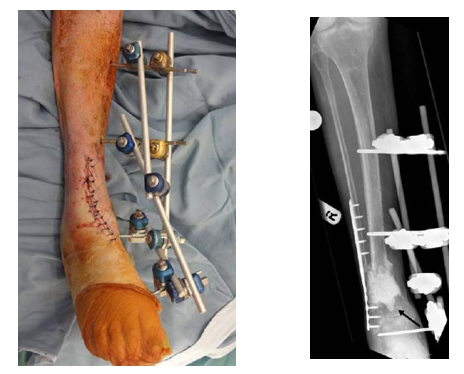

Stage II取出Spacer   混合材料植骨    仔细缝合软组织覆盖良好

髓内钉内固定踝关节融合

技术改进Stage I   直接使用内固定

长节段骨缺损使用Cage作为局部植骨支架

17cm骨缺损